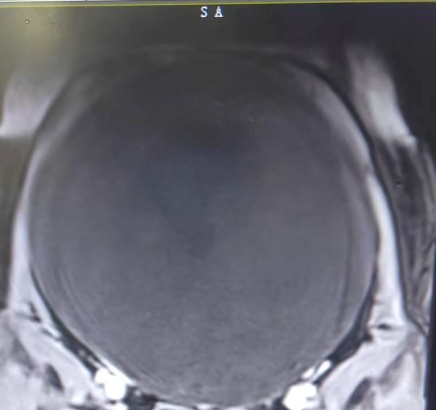

返回上一级 近日,长沙融城医院(原水电八局中心医院)妇科团队成功完成了一例特殊的盆腔巨大包块切除手术,该患者为一名年轻女性,因下腹胀痛、排尿困难等症状前来我院妇科就诊。经过全面且细致的检查,腹部核磁结果显示,其盆腔内竟“藏”着一个直径约30厘米的巨大囊性包块,这一包块严重干扰了患者的日常生活。面对如此棘手的病例,妇科团队在吴昊主任的带领下,经过充分评估,最终决定为该女士实施腹腔镜下盆腔巨大包块切除术。